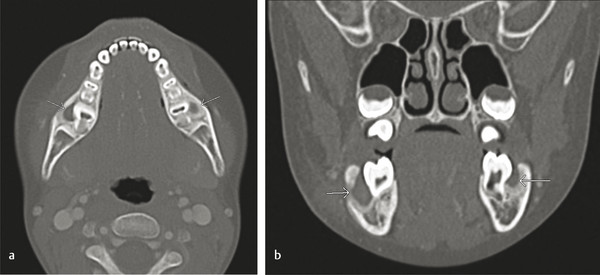

The buccal bifurcation cyst (BBC) is inflammatory rather than developmental and usually develops on the buccal region of vital mandibular first or second molars (Fig. 9‑2). It is usually seen in children between the age of 5 and 15 years. Treatment options include curettage of the lesion with daily irrigation or enucleation and removal of the tooth. They can become secondarily infected and may require antibiotics and surgical drainage of the surrounding tissue.